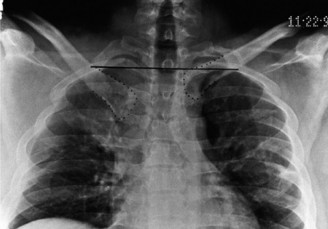

The correct answer is (E). Given that her rotator cuff has atrophied and has fatty infiltration to the point where there are equal parts fat and muscle, this is considered an irreparable rotator cuff tear. Repair should not be attempted because of poor outcomes following repair (see last two paragraphs of this discussion below). A reverse total shoulder arthroplasty is an alternative to repair that should be used in cases of massive, irreparable rotator cuff tears. It is a semi-constrained prosthesis that restores function in patients with massive rotator cuff tears by constraining a concave humeral cap inferior to a semispherical glenoid component (glenosphere). This creates an inferior force-couple and a fulcrum that replaces the stabilizing function of the infraspinatus maintaining a center of rotation around which the shoulder can move. This allows the deltoid to abduct and flex the shoulder without causing the humerus to migrate superiorly and about the acromion. In an elderly patient with a massive, irreparable rotator cuff tear (as in this patient), a reverse total shoulder arthroplasty is the procedure of choice.

It should be noted that reverse total shoulder arthroplasty is also the procedure of choice in patients with cuff-tear arthropathy (aka rotator cuff arthropathy). Characteristics of cuff-tear arthropathy include superior migration of the humerus due to a massive rotator cuff tear, glenohumeral joint destruction, subchondral osteoporosis, and humeral head collapse (see Fig. 2–17). A reverse total shoulder

arthroplasty in this case serves the purpose of eliminating pain caused by glenohumeral joint arthritis while restoring functional motion and is the procedure of choice in patients with cuff-tear arthropathy.

Figure 2–17_X-rays of a patient showing evidence of cuff tear arthropathy. The humerus is migrated superiorly, the glenohumeral joint is destroyed, there is subchondral osteoporosis, and the humeral head is collapsed. (From Ecklund KJ, Lee TQ, Tibone J, Gupta R. Rotator cuff tear arthropathy. _J Am Acad Orthop Surg. 2007;15(6):340–349.)